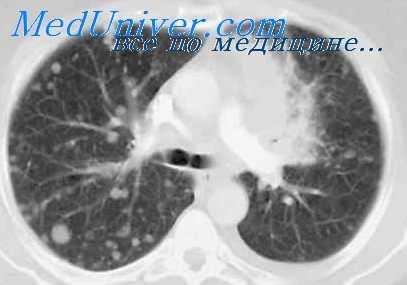

Высокое качество боковой бронхограммы, выполняемой поданной методике, объясняется также тем, что в положении, когда исследуемое легкое оказывается вышележащим, значительно ослабевает передаточная пульсация бронхов. Это особенно хорошо заметно на бронхограммах левого легкого.

Заполнение бронхов контрастным веществом при исследовании больного на трохоскопе производится, как и при обычной методике, после поворота больного на бок. Однако в данном случае нет необходимости применять боковую бронхограмму, располагая рентгеновскую пленку с противоположной исследуемой стороны.

Надувные манжетки, изолирующие дыхательные пути каждого легкого, исключают затекание контрастного вещества во время исследования в бронхи второго легкого. Благодаря этому, заполнив бронхи нижележащего легкого, мы поворачиваем больного на спину и производим бронхографию в прямой проекции. Затем под контролем экрана совершаем поворот больного в боковое положение, при котором исследуемое легкое становится вышележащим, то есть максимально приближенным к рентгеновской пленке. В этом положении осуществляют боковую бронхограмму.

30 больным, исследованным по данной методике, мы производили две боковые бронхограммы: первая — со стороны, противоположной исследуемому легкому, иначе говоря, по общепринятой методике, и вторая — со стороны исследуемого легкого.